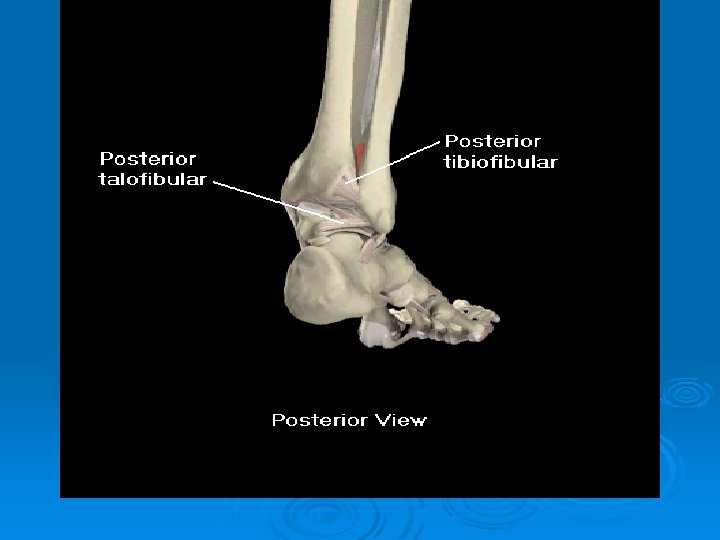

Lateral Ligaments of the Ankle Ø Resist ankle inversion Ø Anterior talofibular (ATF) l Most commonly sprained Calcaneofibular (CF) Ø Posterior talofibular (PTF) Ø